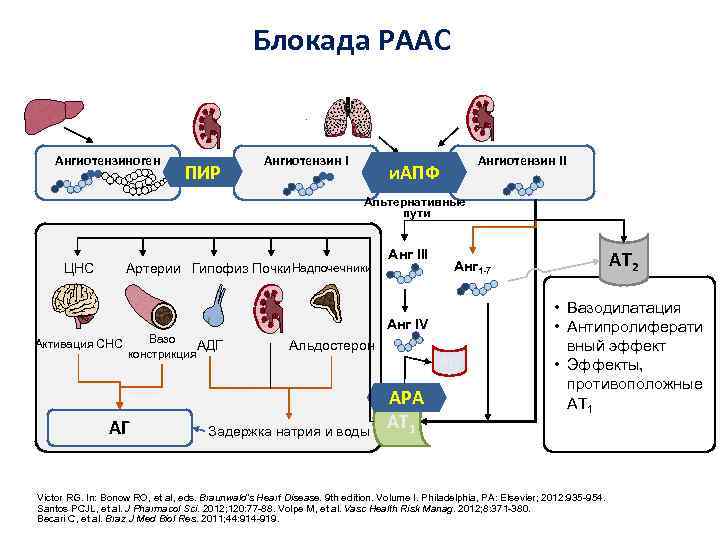

Блокада РААС Ангиотензиноген ПИР Ангиотензин II и. АПФ Альтернативные пути ЦНС Артерии Гипофиз Почки Надпочечники Анг III Анг IV Вазо Активация СНС АДГ констрикция АГ Альдостерон Задержка натрия и воды AT 4 АРА AT 1 AT 2 Анг 1 -7 • Вазодилатация • Антипролиферати вный эффект • Эффекты, противоположные AT 1 Victor RG. In: Bonow RO, et al, eds. Braunwald’s Heart Disease. 9 th edition. Volume I. Philadelphia, PA: Elsevier; 2012: 935 -954. Santos PCJL, et al. J Pharmacol Sci. 2012; 120: 77 -88. Volpe M, et al. Vasc Health Risk Manag. 2012; 8: 371 -380. Becari C, et al. Braz J Med Biol Res. 2011; 44: 914 -919.

Блокада РААС Ангиотензиноген ПИР Ангиотензин II и. АПФ Альтернативные пути ЦНС Артерии Гипофиз Почки Надпочечники Анг III Анг IV Вазо Активация СНС АДГ констрикция АГ Альдостерон Задержка натрия и воды AT 4 АРА AT 1 AT 2 Анг 1 -7 • Вазодилатация • Антипролиферати вный эффект • Эффекты, противоположные AT 1 Victor RG. In: Bonow RO, et al, eds. Braunwald’s Heart Disease. 9 th edition. Volume I. Philadelphia, PA: Elsevier; 2012: 935 -954. Santos PCJL, et al. J Pharmacol Sci. 2012; 120: 77 -88. Volpe M, et al. Vasc Health Risk Manag. 2012; 8: 371 -380. Becari C, et al. Braz J Med Biol Res. 2011; 44: 914 -919.